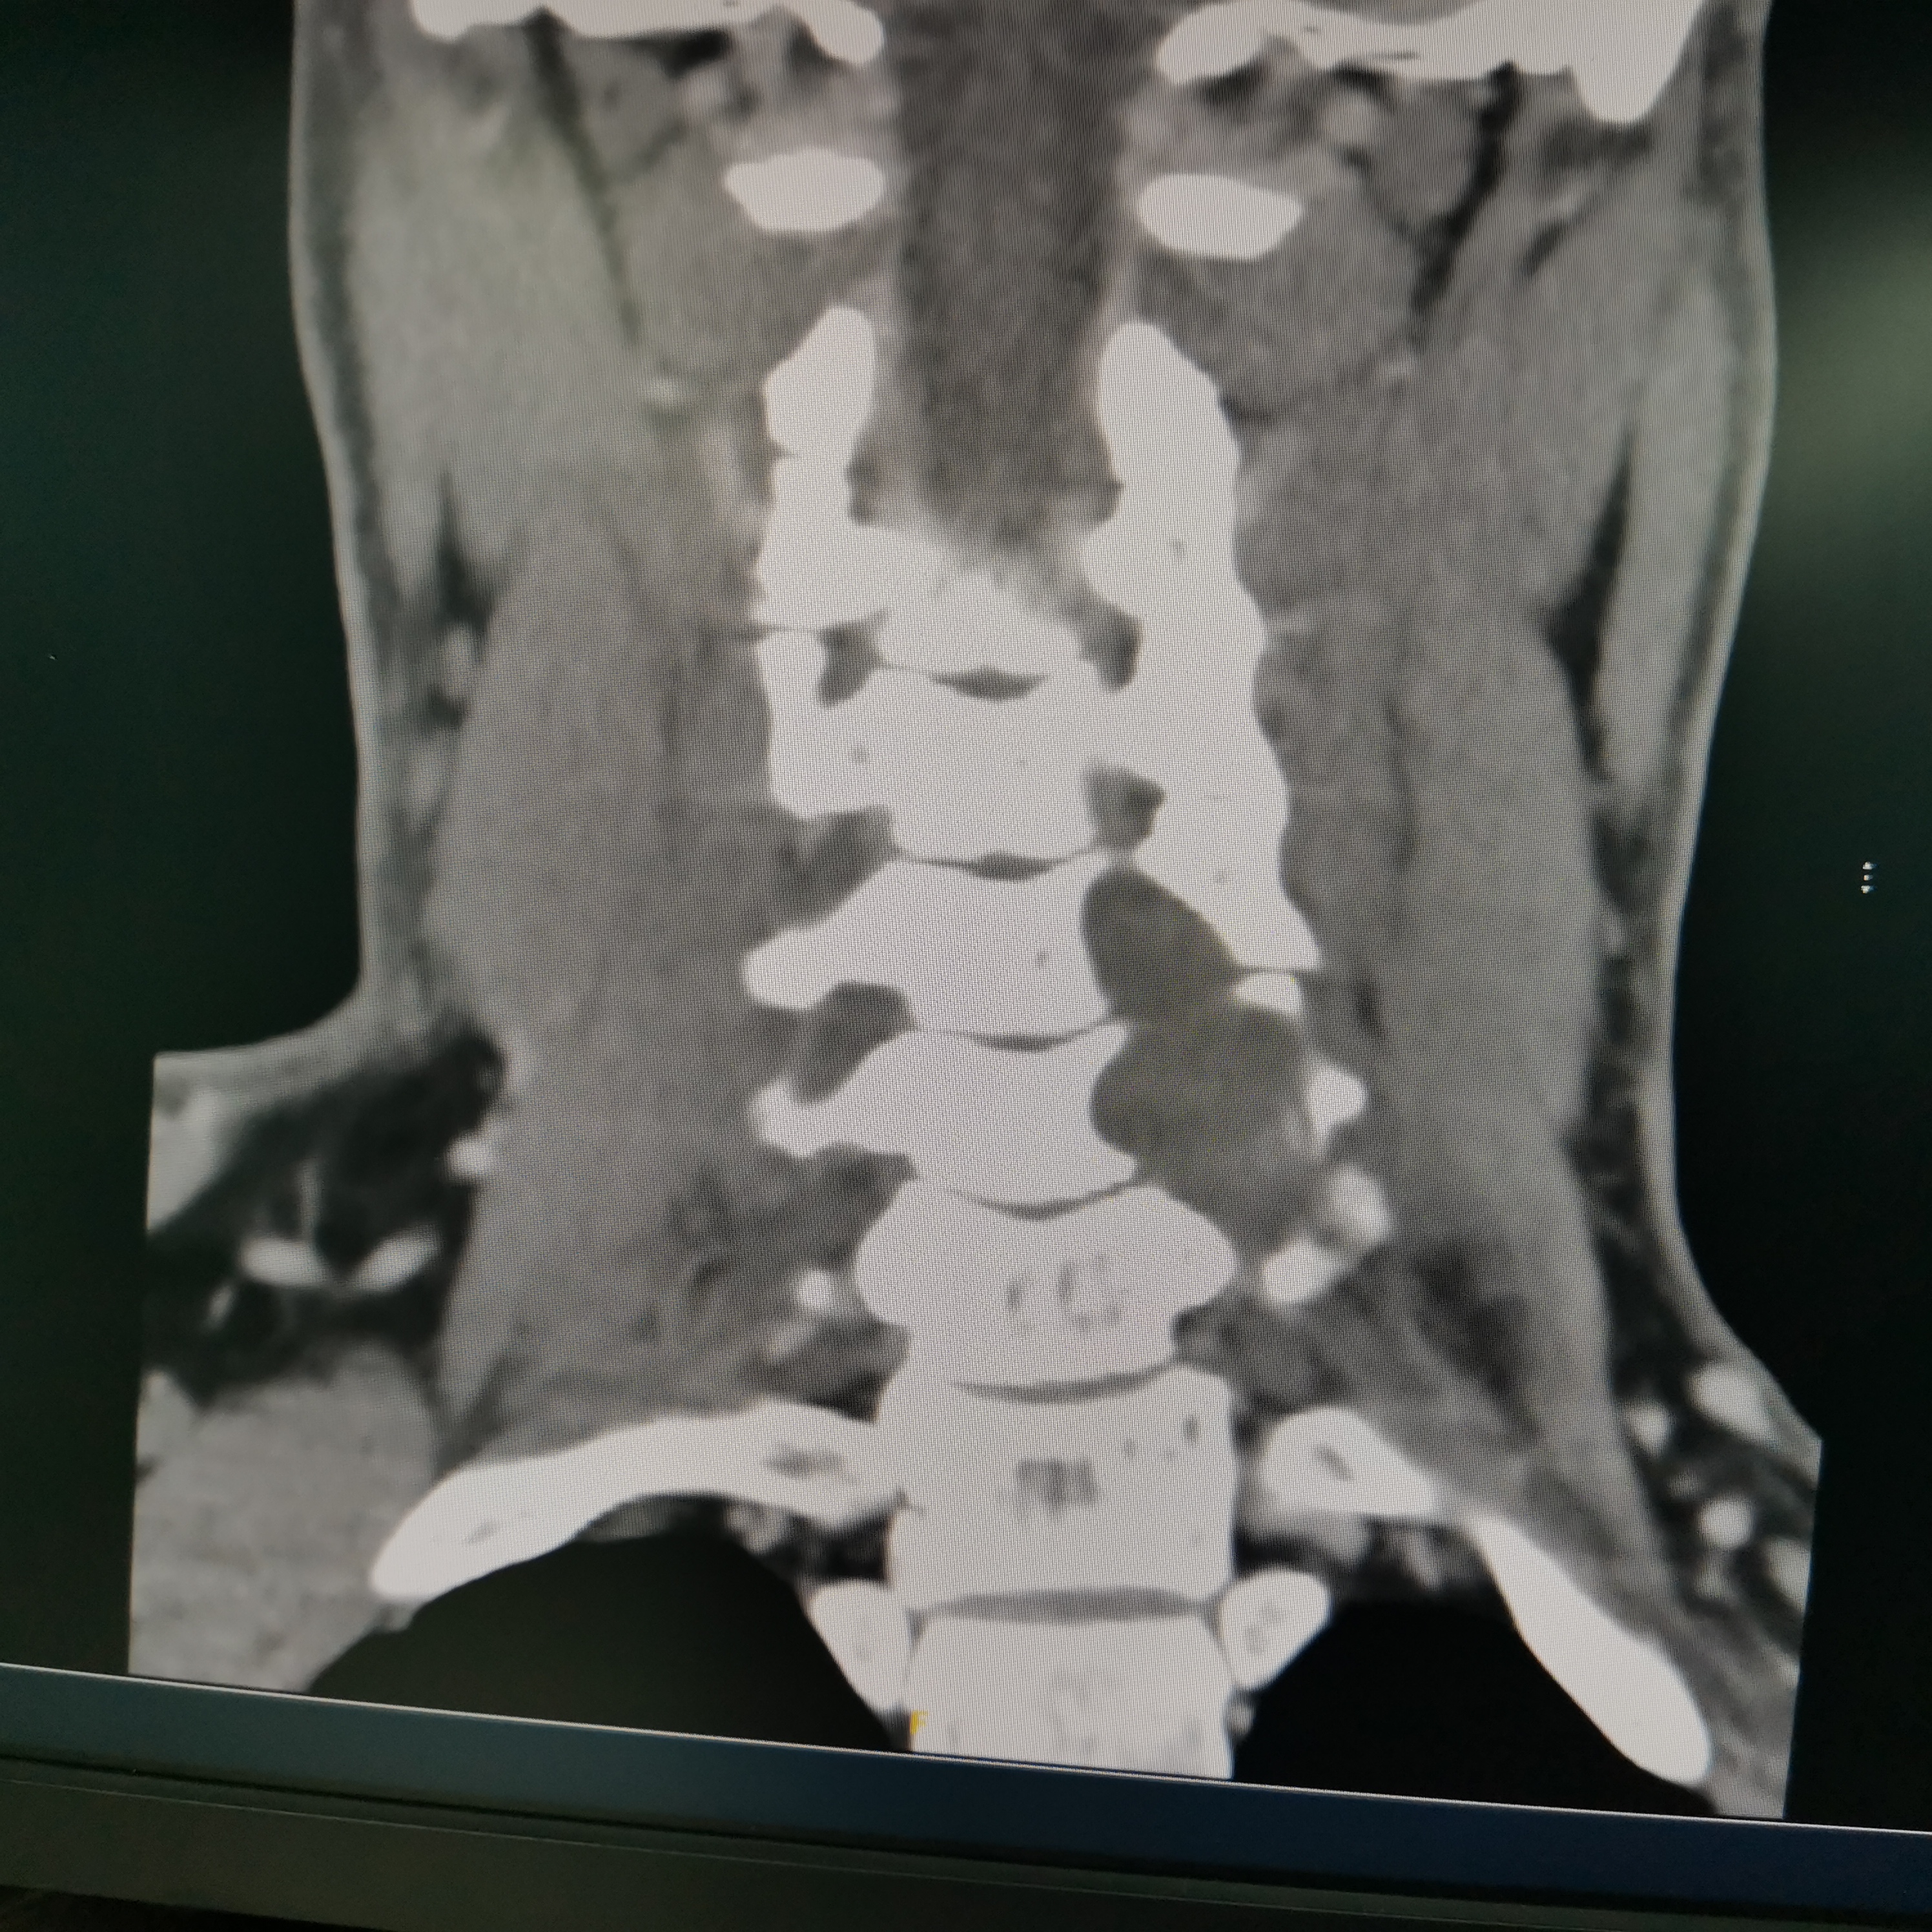

颈椎哑铃型神经纤维瘤,椎间孔汇合,安全又便于操作~